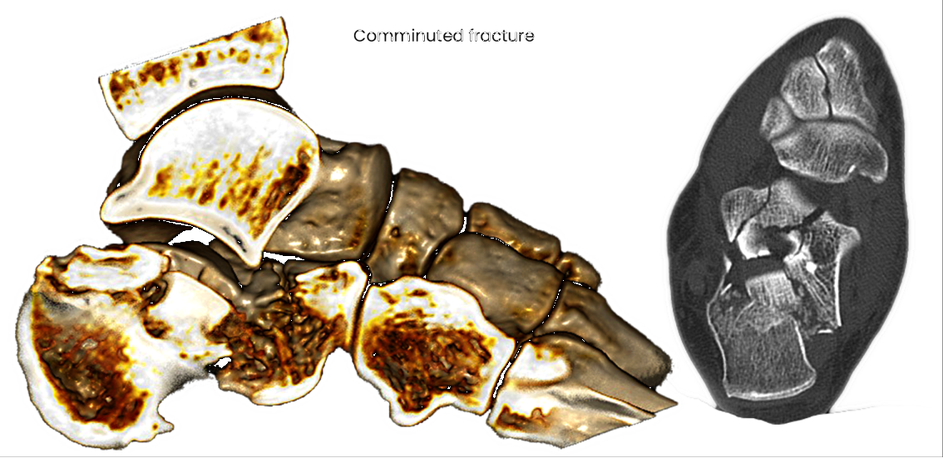

case 17BD, 47 years old, male, fall during work, 2 meters, "comminuted fracture", surgery after 2 days